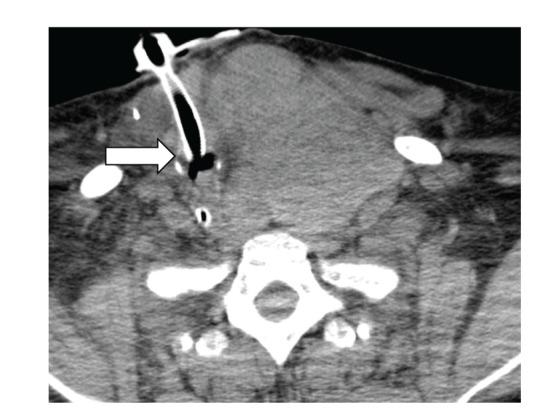

Acute upper airway obstruction is a medical emergency and can be caused by many serious conditions such as a foreign body occluding the airway, intrinsic swelling (as in anaphylaxis), or extrinsic compression. Thyromegaly has rarely been reported as a source of airway compromise. We present a patient whose thyromegaly is presumed to have been induced by lithium and was massive enough to cause severe airway compromise.

急性上气道梗阻是一种医疗急症,可由许多严重情况引起,如气道被异物阻塞、内在肿胀(如过敏反应)或外在压迫。甲状腺肿大作为气道受损的原因鲜有报道。我们报告一例患者,其甲状腺肿大推测由锂盐诱发,肿大程度足以导致严重的气道受损。